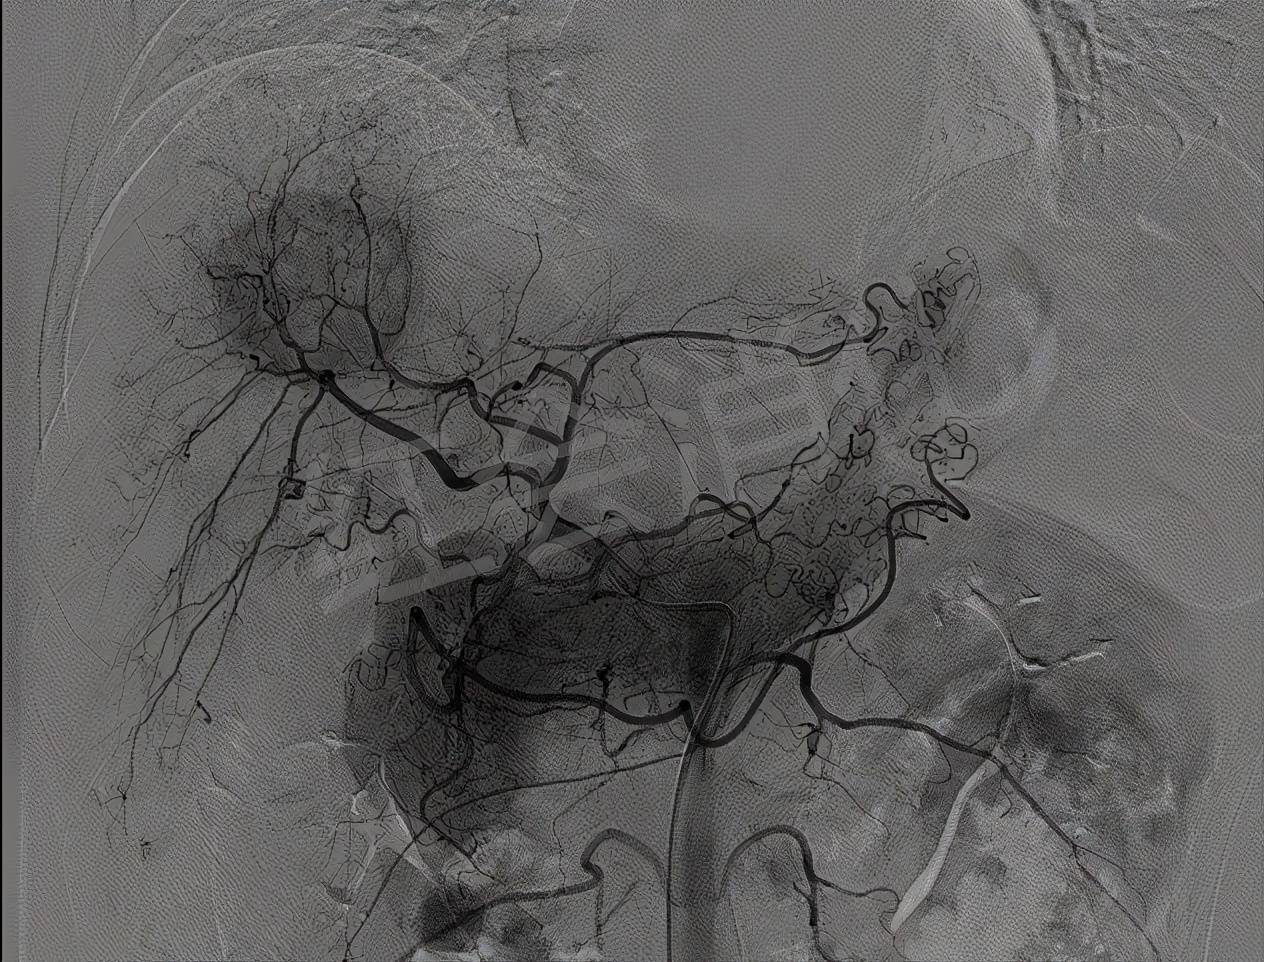

栓塞前肝动脉造影 , 可见明显的动脉丛 , 成“球形”包绕

文章图片

超选肿瘤供血动脉造影 , 可见肿瘤染色明显 , 予以灌注化疗栓塞治疗